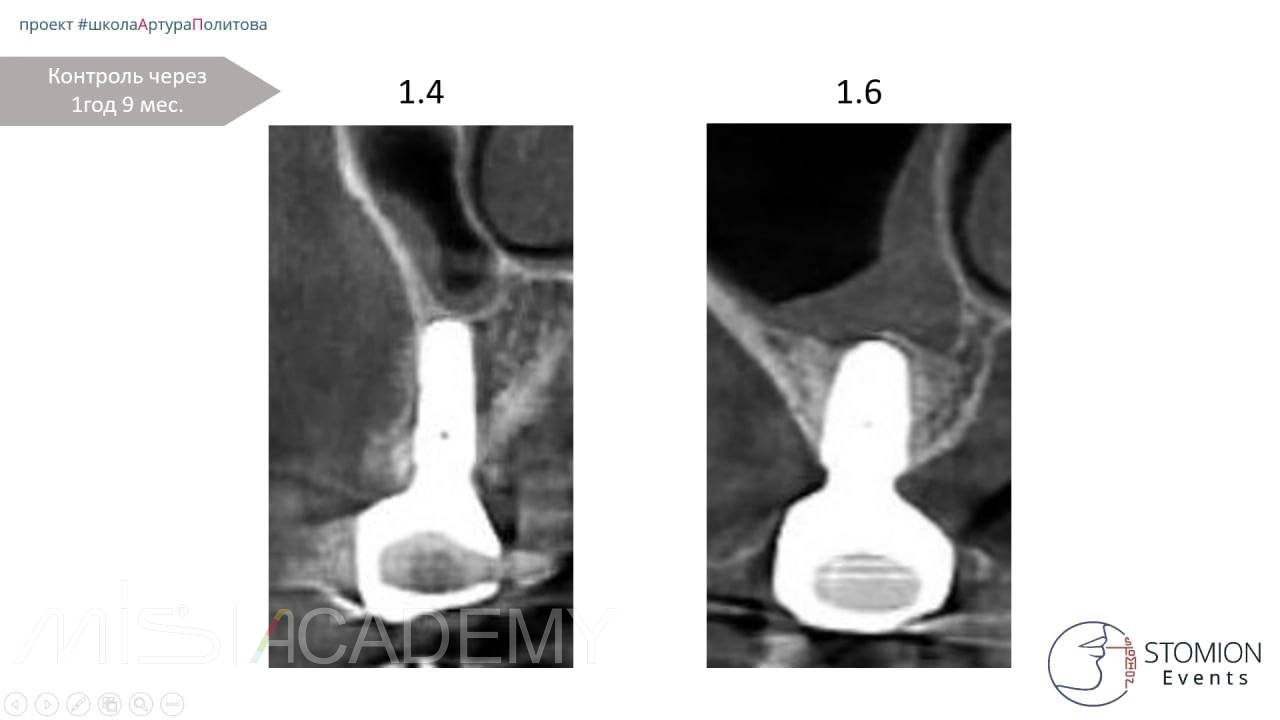

Одномоментная имплантация 2.5, 3.6, 4.6.